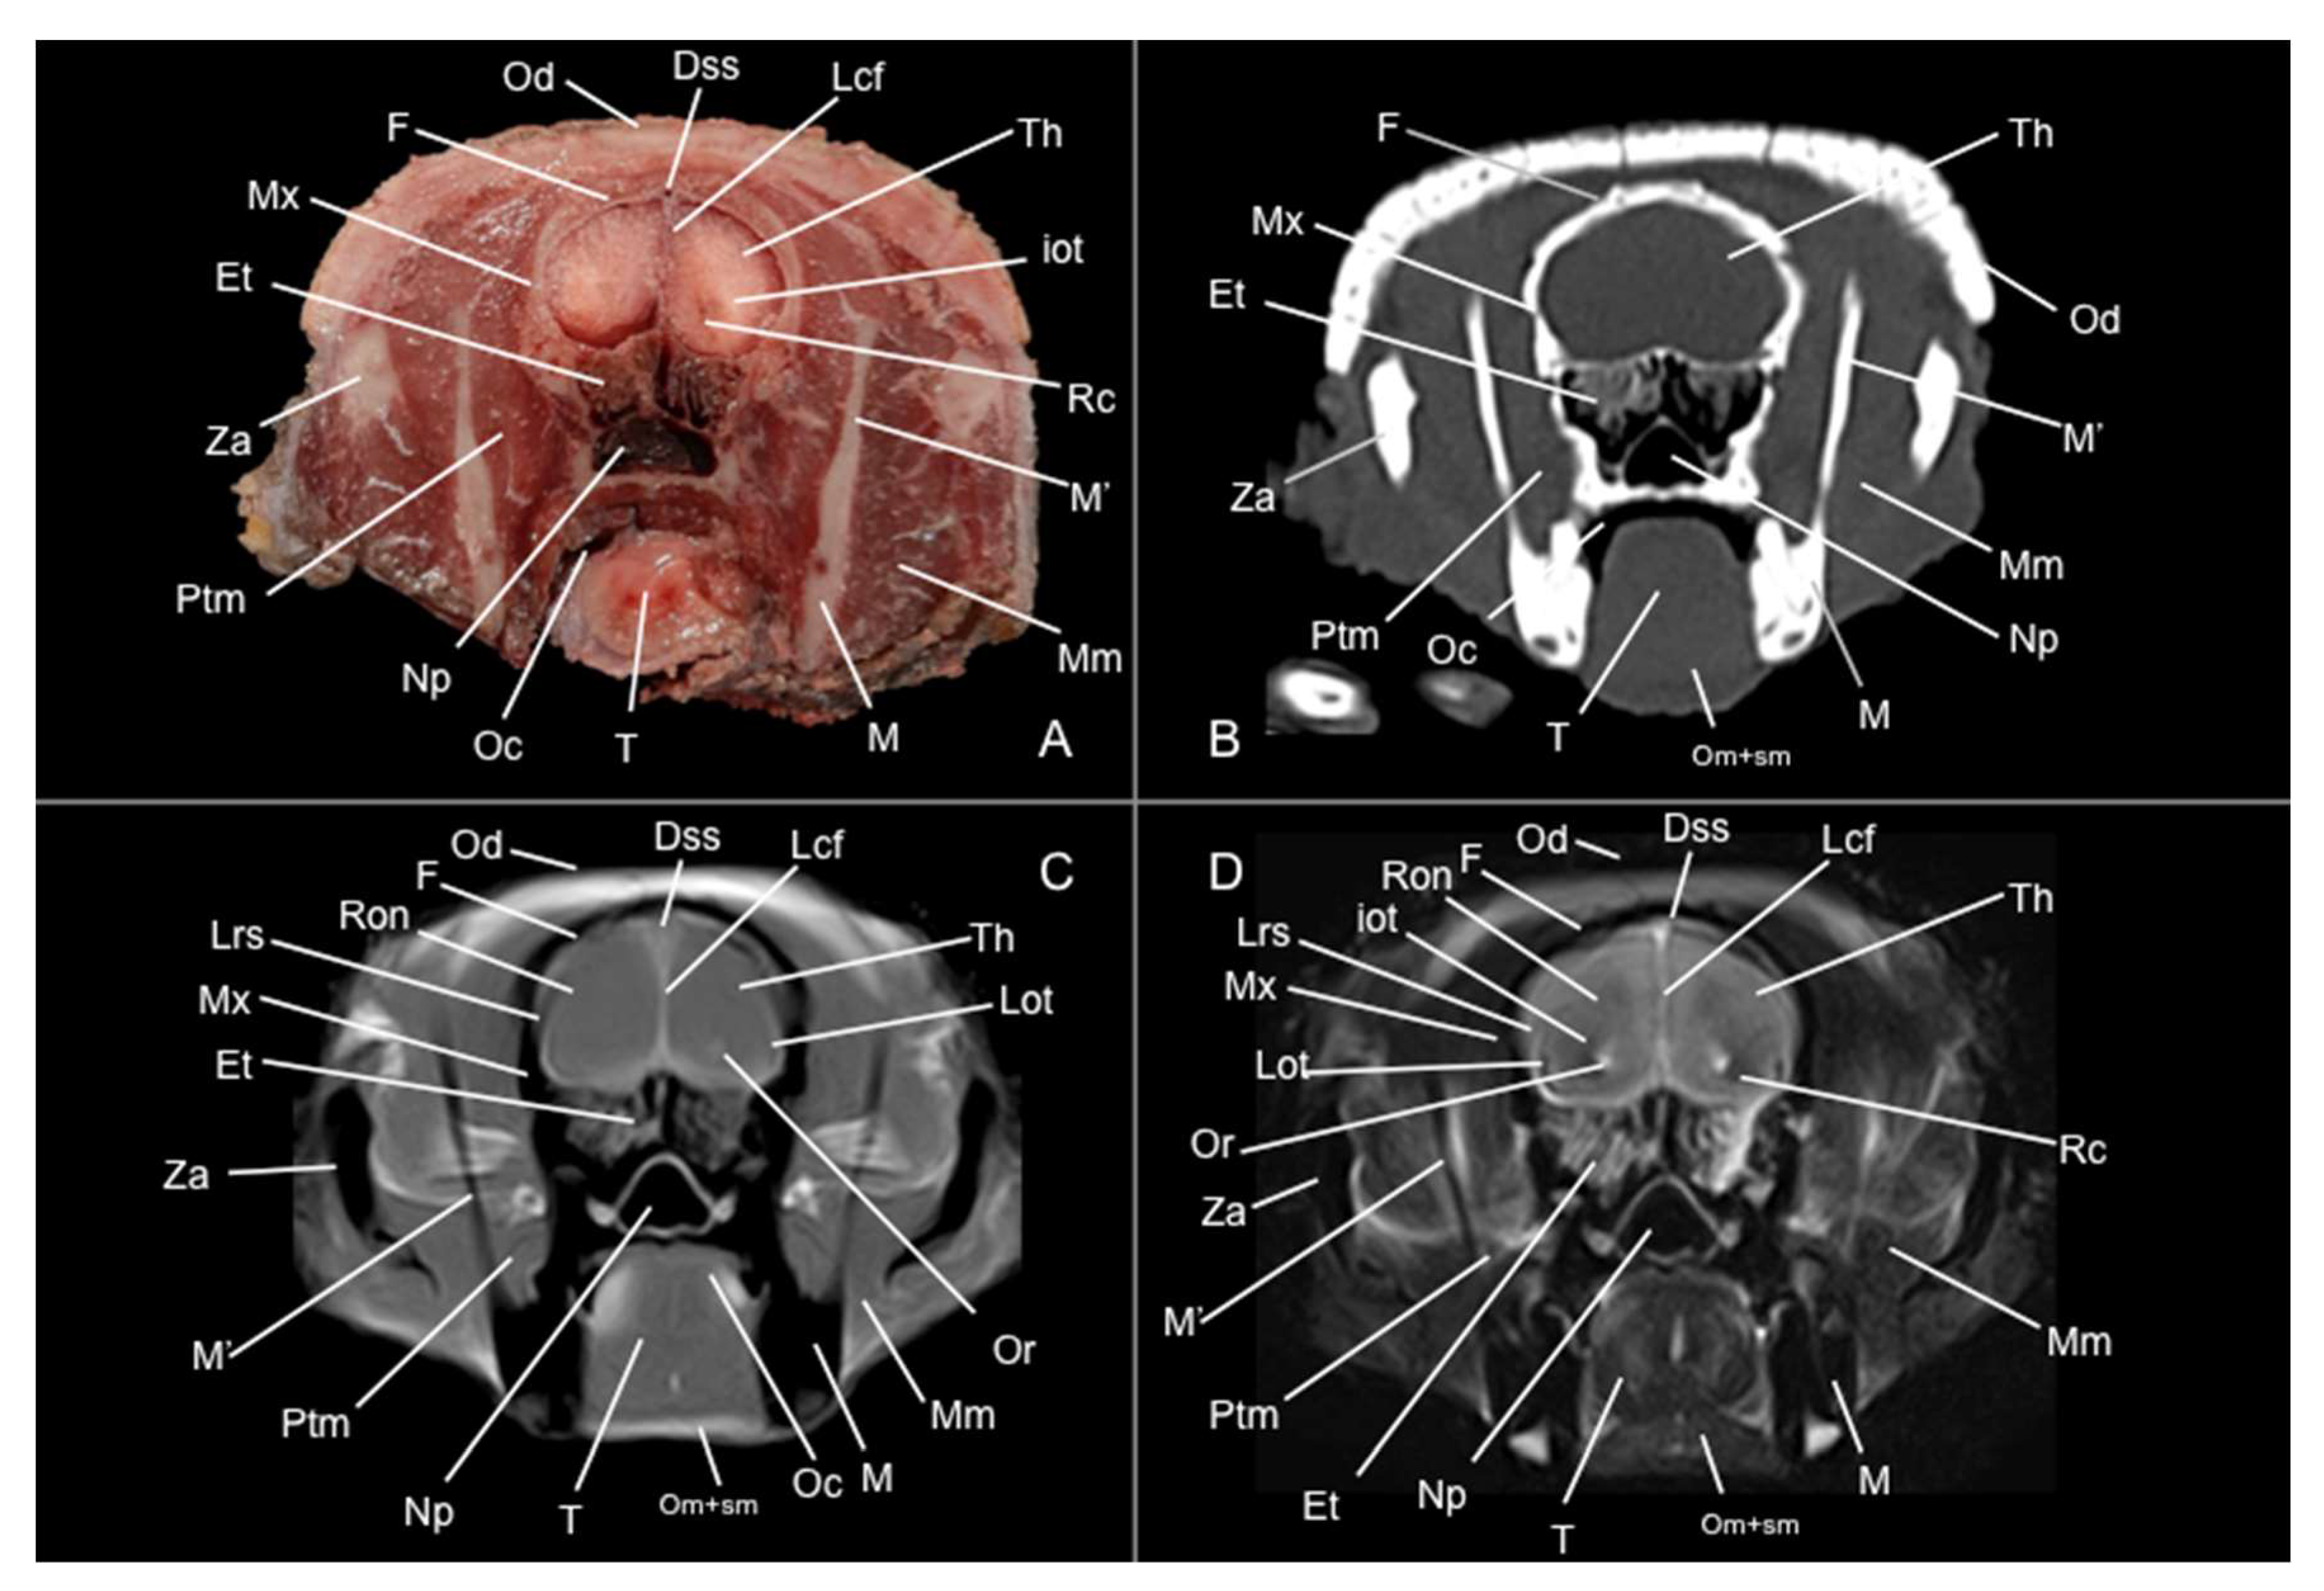

3.1. Anatomical Sections

3.2. Computed Tomography Study

3.3. Magnetic Resonance Imaging (MRI)